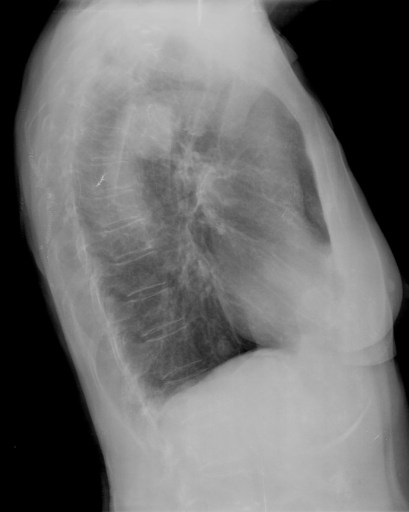

Nota: ¡¡¡No olvidar la placa lateral!!! La regla a seguir es la misma. Leer abdomen y diafragma, examinar parte posterior, tejidos blandos y subir por la columna; tráquea y descender por mediastino. Finalmente pulmones.

Solución: Es un estudio Normal. Silueta cardiomediastínica y parénquimas pulmonares sin alteraciones significativas.